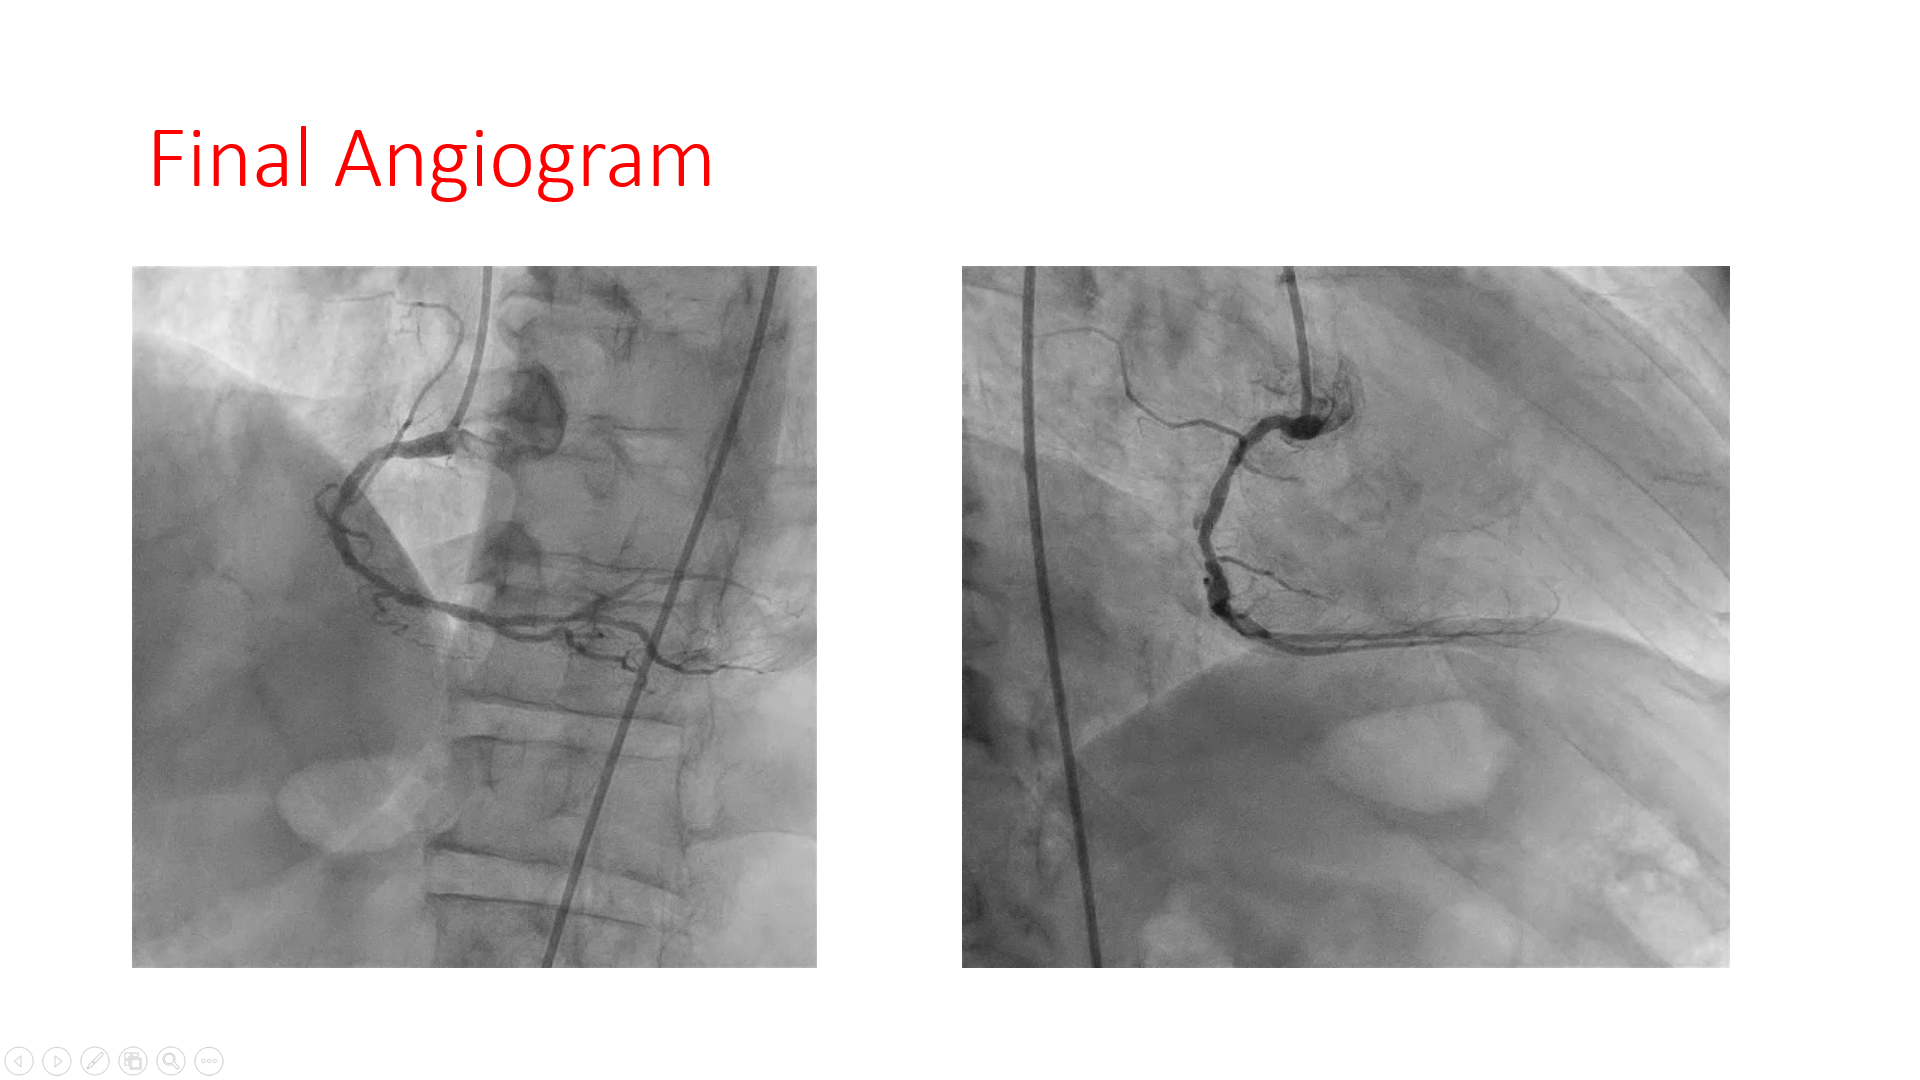

7F Femoralapproach and AL 0.75 was taken. Lesion crossed with Runthrough wire with fine cross support. Predicated with 1.5*5mm semicomplaint balloon , could not crossed and busted distally. ROTA 1.5mmburr, couldn't crossed at mid RCA, even at 200000 rpm speed, likely wire bias. ROTA 1.25mm burr crossed at 150000 rpm and after that, lesion was predilated with 2.5*15 mm semicomplaint balloon, and 2.75*15 mm non complaint balloon. Stent 2.5*38mm was deployed in distal-mid RCA at 12 atm, and proximal stent 3*32 mm was deployed in mid-proximal RCA at nominal pressure with Guidezilla support.Post stent dilation was done distally with 3*15 mm and proximally with 3.5x15mm Non-complaint balloon @ 16-18 atm. Good end result.

Case Summary

Step-down Rota burr strategy should be done early, in case of difficulty with regular burr. Wire bias does exist during Rota ablation. Tortuosity in vessel predisposes to wire bias in rotablation. Changing the wire to extra support or reducing the burr size: what should be done ideally and always matter of discussion.